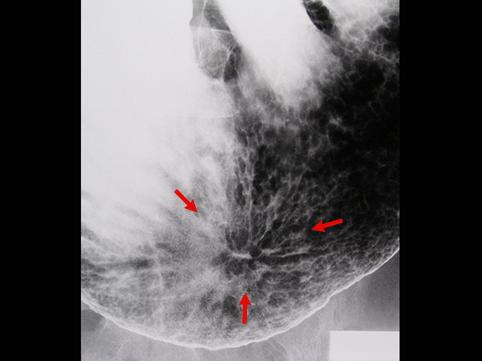

Criteria of Hist.ClassificationMalignant epithelial tumor/Adenocarcinoma

LocationStomach/Angle

Technique, MethodX-ray

Macroscopic TypesType 0/IIc (IIc) Superficial depressed type

Size30 - 34

Depth of Tumor Invasionmucosa